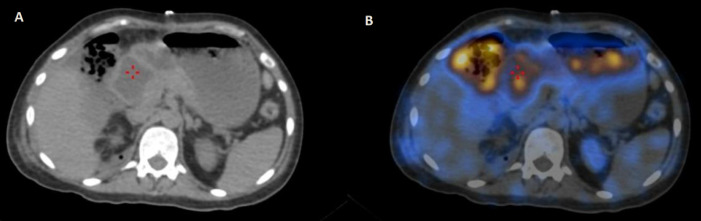

Perforation of the bowel can be a life-threatening condition and is usually clinically diagnosed when a patient presents with such features as severe abdominal pain, tenderness, and tachycardia. Bowel perforation may be corroborated by various conventional imaging modalities, including X-ray, ultrasonography, computed tomography, and magnetic resonance imaging. Nuclear medicine imaging modalities seldom have a role to play in these settings. Rarely diagnosis of perforation may be missed if it is concealed and does not present with the usual signs. Mostly the perforation will eventually be diagnosed if they develop signs and symptoms and is taken up for an exploratory laparotomy. A delay in diagnosis can later lead to significant patient morbidity or even mortality. This report describes a case where possible intestinal perforation was suspected on a 99mTc-DTPA renogram in a postoperative patient with significant urine leak, the presence of which was confirmed intraoperatively. To our knowledge, this was the first such case in the literature.